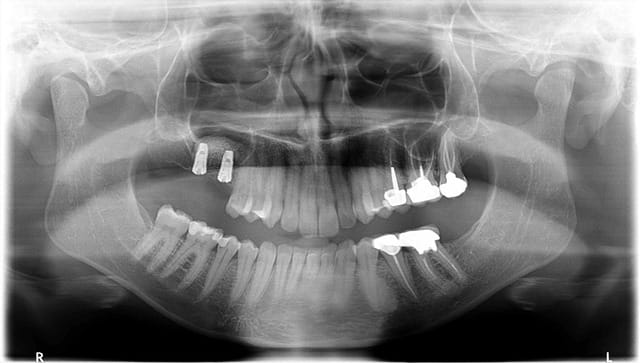

bonsoir

je voulais partager avec vous ce cas de soulevé sinusien par voie latérale avec implantation immédiate qui est possible malgré la faible quantité osseuse résiduelle comme on peut s'en rendre compte sur la 3D grâce aux caractéristiques de l'implant.

on peut noter sur la dernière pano qui est réalisée à 2 mois post op la densification du matériau qui peut s'expliquer de différentes manières:

- la petite fenêtre réalisée (technique DASK)

- le matériau OSTEON qui est un biphasé dont chaque particule d'HA est enrobée de béta TCP ce qui rend son intégration plus rapide

suite du cas

la patiente revient enfin pour vous montrer la suite

voici la radio de controle ( rétro) des piliers de cicat